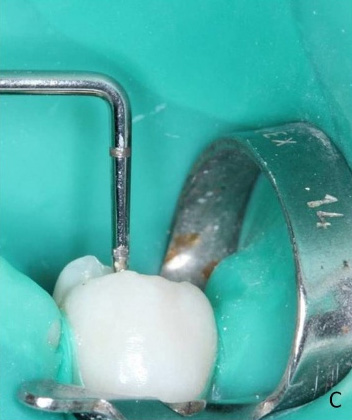

Figure 3C. Insertion of the material in the root canal.